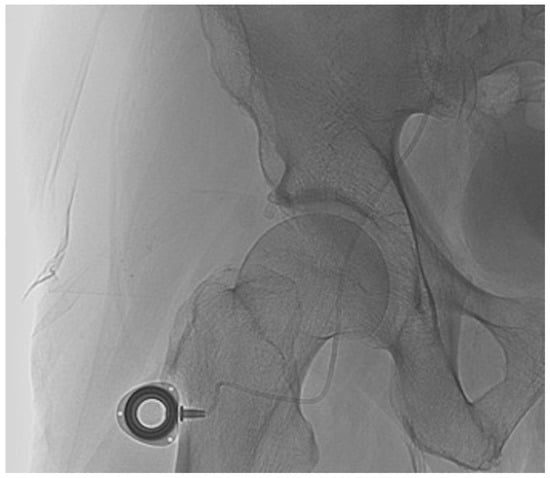

Percutaneous Implantation of a Microcatheter-Port System for Hepatic Arterial Infusion Chemotherapy of Unresectable Liver Tumors: Technical Feasibility, Functionality, and Complications

2.2. Percutaneous Microcatheter-Port System Implantation